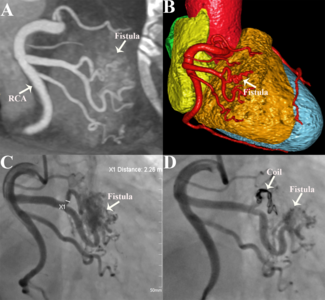

A 70-year-old man presented with persistent exertional angina. He had undergone coronary artery bypass grafting 14 years ago, with a left internal mammary artery graft to the left anterior descending artery and a saphenous vein Y-graft to the...